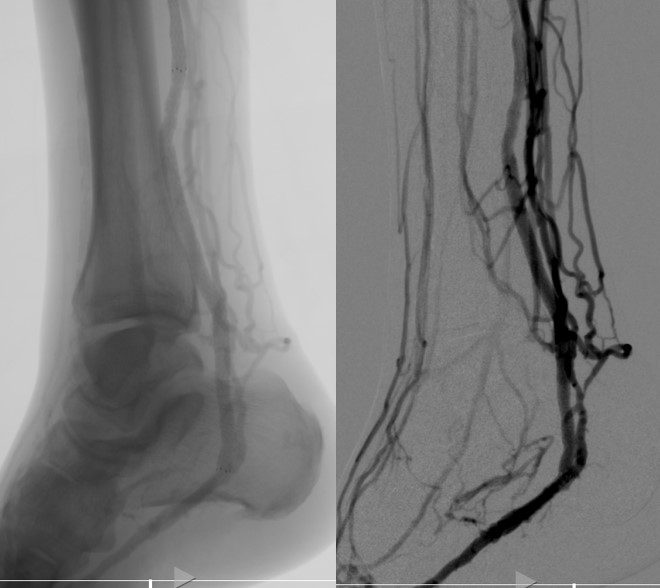

The LimFlow System uses a series of stents and devices to bypass permanently blocked arteries in the leg and foot. By rerouting oxygen-rich blood through the veins, surgeons can revascularize tissue that would otherwise be lost.

“This technology essentially turns the vein into an artery, allowing us to restore circulation without major surgery,” said Dr. Raible. “It’s been incredibly inspiring to see patients regain hope and mobility.”